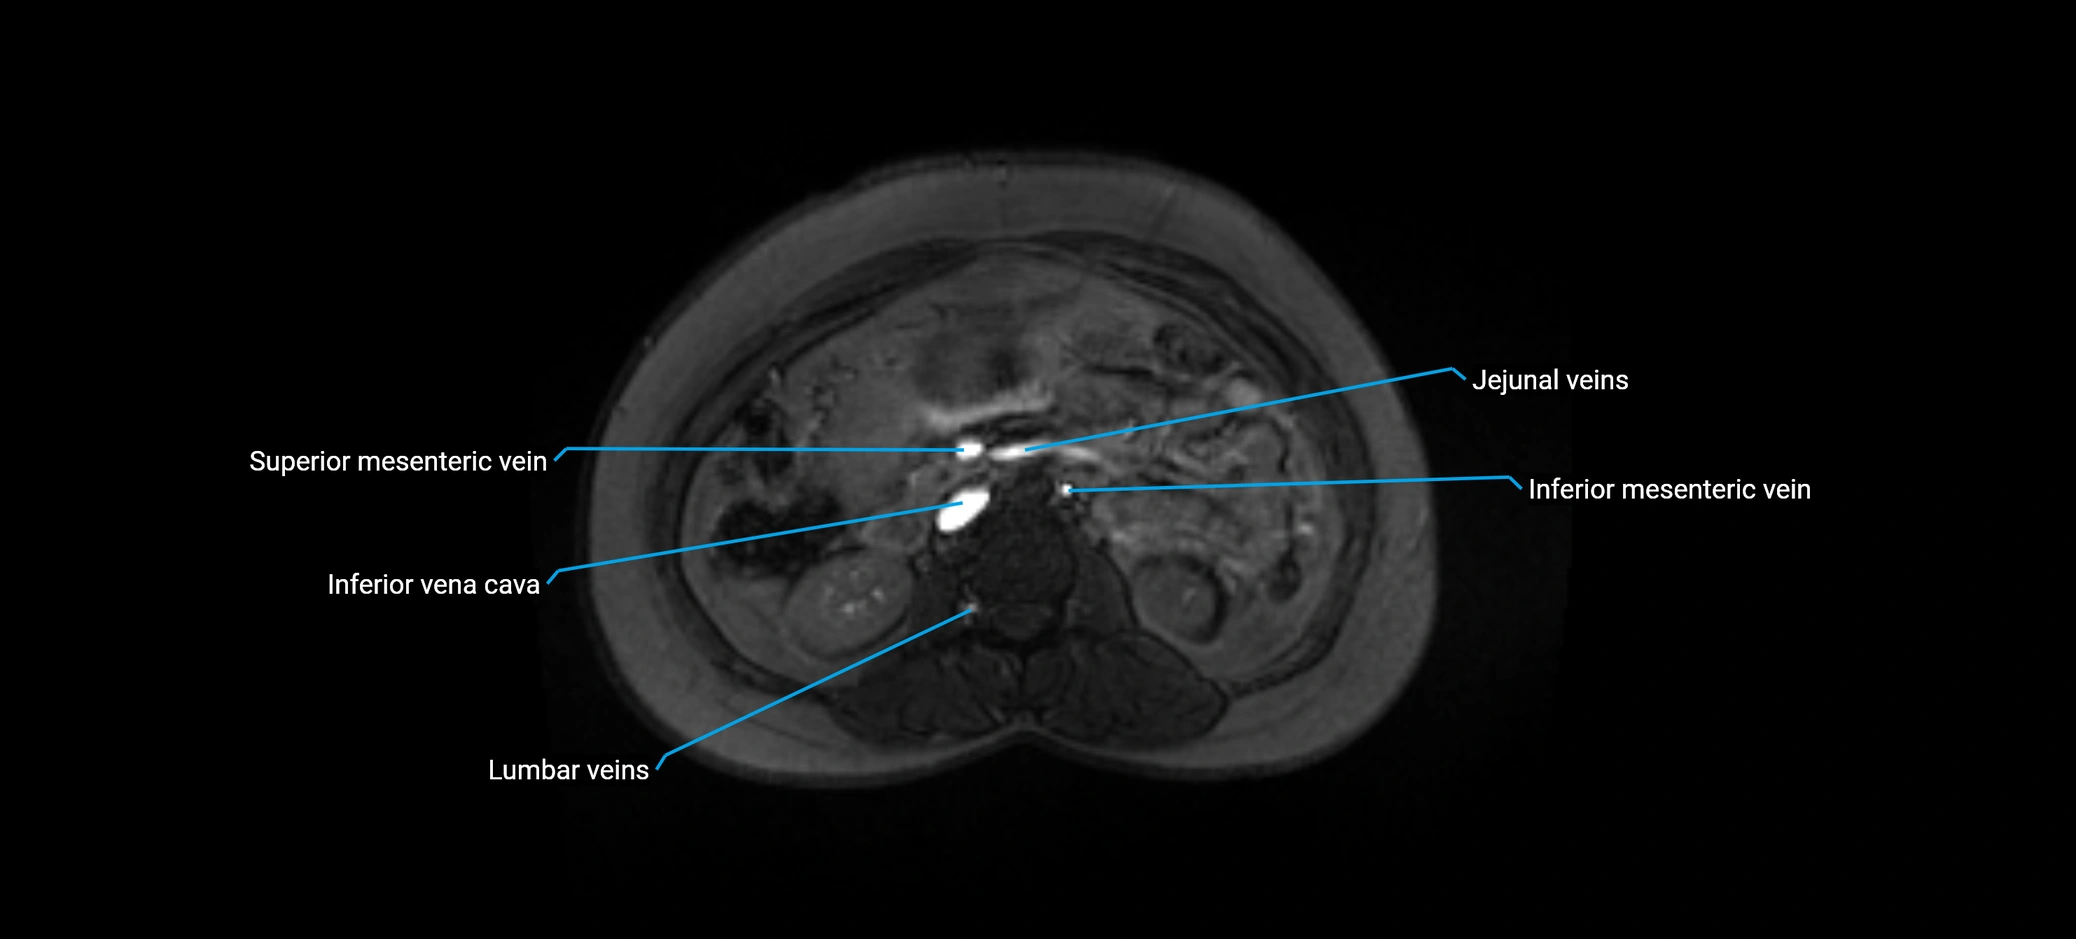

MRI image

image